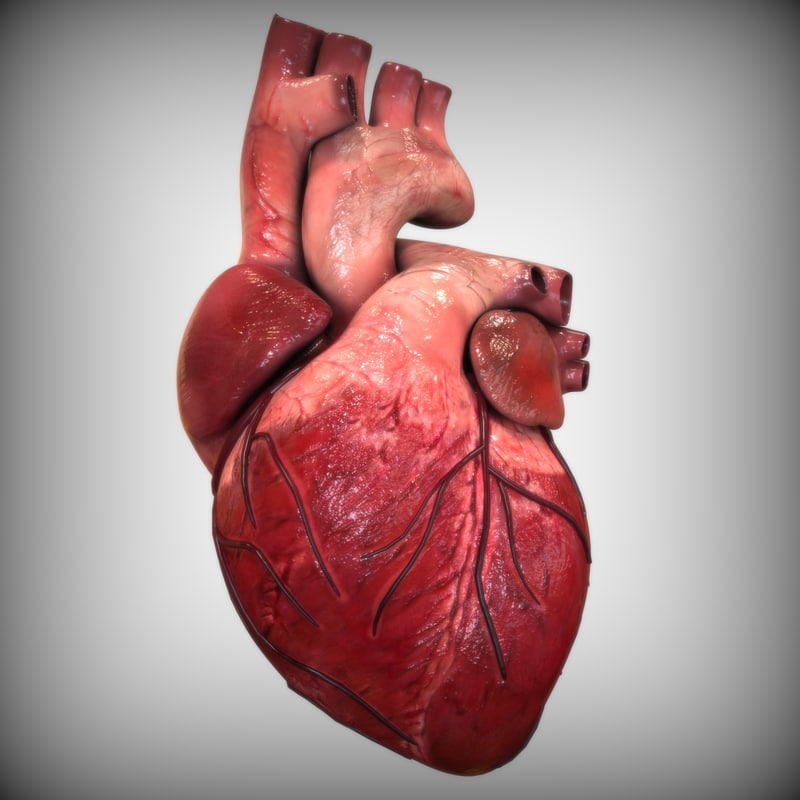

Human Heart Sketchbook study by bluesytealyren on DeviantArt | Human heart drawing, Anatomical  3d human heart

3d human heart  Animated Realistic Human Heart - Medically 3D asset

Animated Realistic Human Heart - Medically 3D asset  Zygote::3D Heart Model | Medically Accurate | Human Anatomy

Zygote::3D Heart Model | Medically Accurate | Human Anatomy  Zygote::Solid 3D Human Heart Model

Zygote::Solid 3D Human Heart Model  3D human heart anatomy model - TurboSquid 1283134

3D human heart anatomy model - TurboSquid 1283134  anatomy human heart 3d c4d

Human Heart Anatomy 1 3D model | CGTrader  How to draw realistic human heart||3d human heart sketch

Realistic Human Heart 3D model | CGTrader  anatomy human heart 3d c4d

Human Heart Anatomy 1 3D model | CGTrader  human heart anatomy 3d max